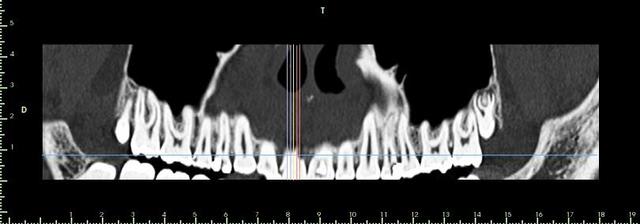

encore un ptit cas...sympa si on veut...car là j'ai besoin de l'expérience de ceux qui font çà souvent...

patient 17 ans...bientôt 18...

trauma dans l'enfance sur 11 et 21

pour la 21, çà va...mais la 11 est à bout de souffle...avec l'apex qui traverse la gencive vestibulaire...

veut un implant...forcément...mais là, faut une greffe...plutôt importante...

je pencherais plutôt pour un bloc fixé avec des vis d'ostéosynthèses...par contre, je suis pas chaud (et lui non plus) pour aller prélever au menton ou sur la branche montante...